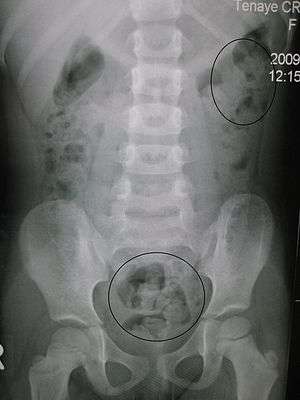

Constipation in a young child as seen by X-ray. Circles represent areas of fecal matter (stool is opaque white surrounded by black bowel gas).

Significant constipation in an 8 year old as seen on plain X ray

The diagnosis is essentially made from the patient's description of the symptoms. Bowel movements that are difficult to pass, very firm, or made up of small hard pellets (like those excreted by rabbits) qualify as constipation, even if they occur every day. Other symptoms related to constipation can include bloating, distension, abdominal pain, headaches, a feeling of fatigue and nervous exhaustion, or a sense of incomplete emptying.[23]

During physical examination, scybala[24] (manually palpable lumps of stool) may be detected on palpation of the abdomen. Rectal examination gives an impression of the anal sphincter tone and whether the lower rectum contains any feces or not. Rectal examination also gives information on the consistency of the stool, the presence of hemorrhoids, admixture of blood and whether any tumors, polyps or abnormalities are present. Physical examination may be done manually by the physician, or by using a colonoscope. X-rays of the abdomen, generally only performed if bowel obstruction is suspected, may reveal extensive impacted fecal matter in the colon, and confirm or rule out other causes of similar symptoms.[7][8]